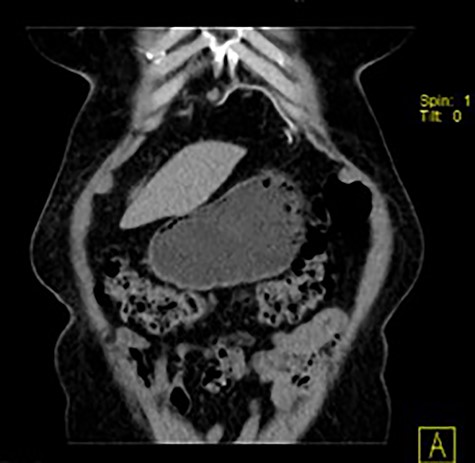

Follow-up at the first and fourth postoperative months, remaining clinically asymptomatic. At the fourth postoperative month, she had a follow-up thoracic and abdominal CT done (Fig. 5) that confirmed no mesh migration nor hernia recurrence.

Coronal image of thoracic and abdominal CT showing the location of the mesh (linear and hyperdense).